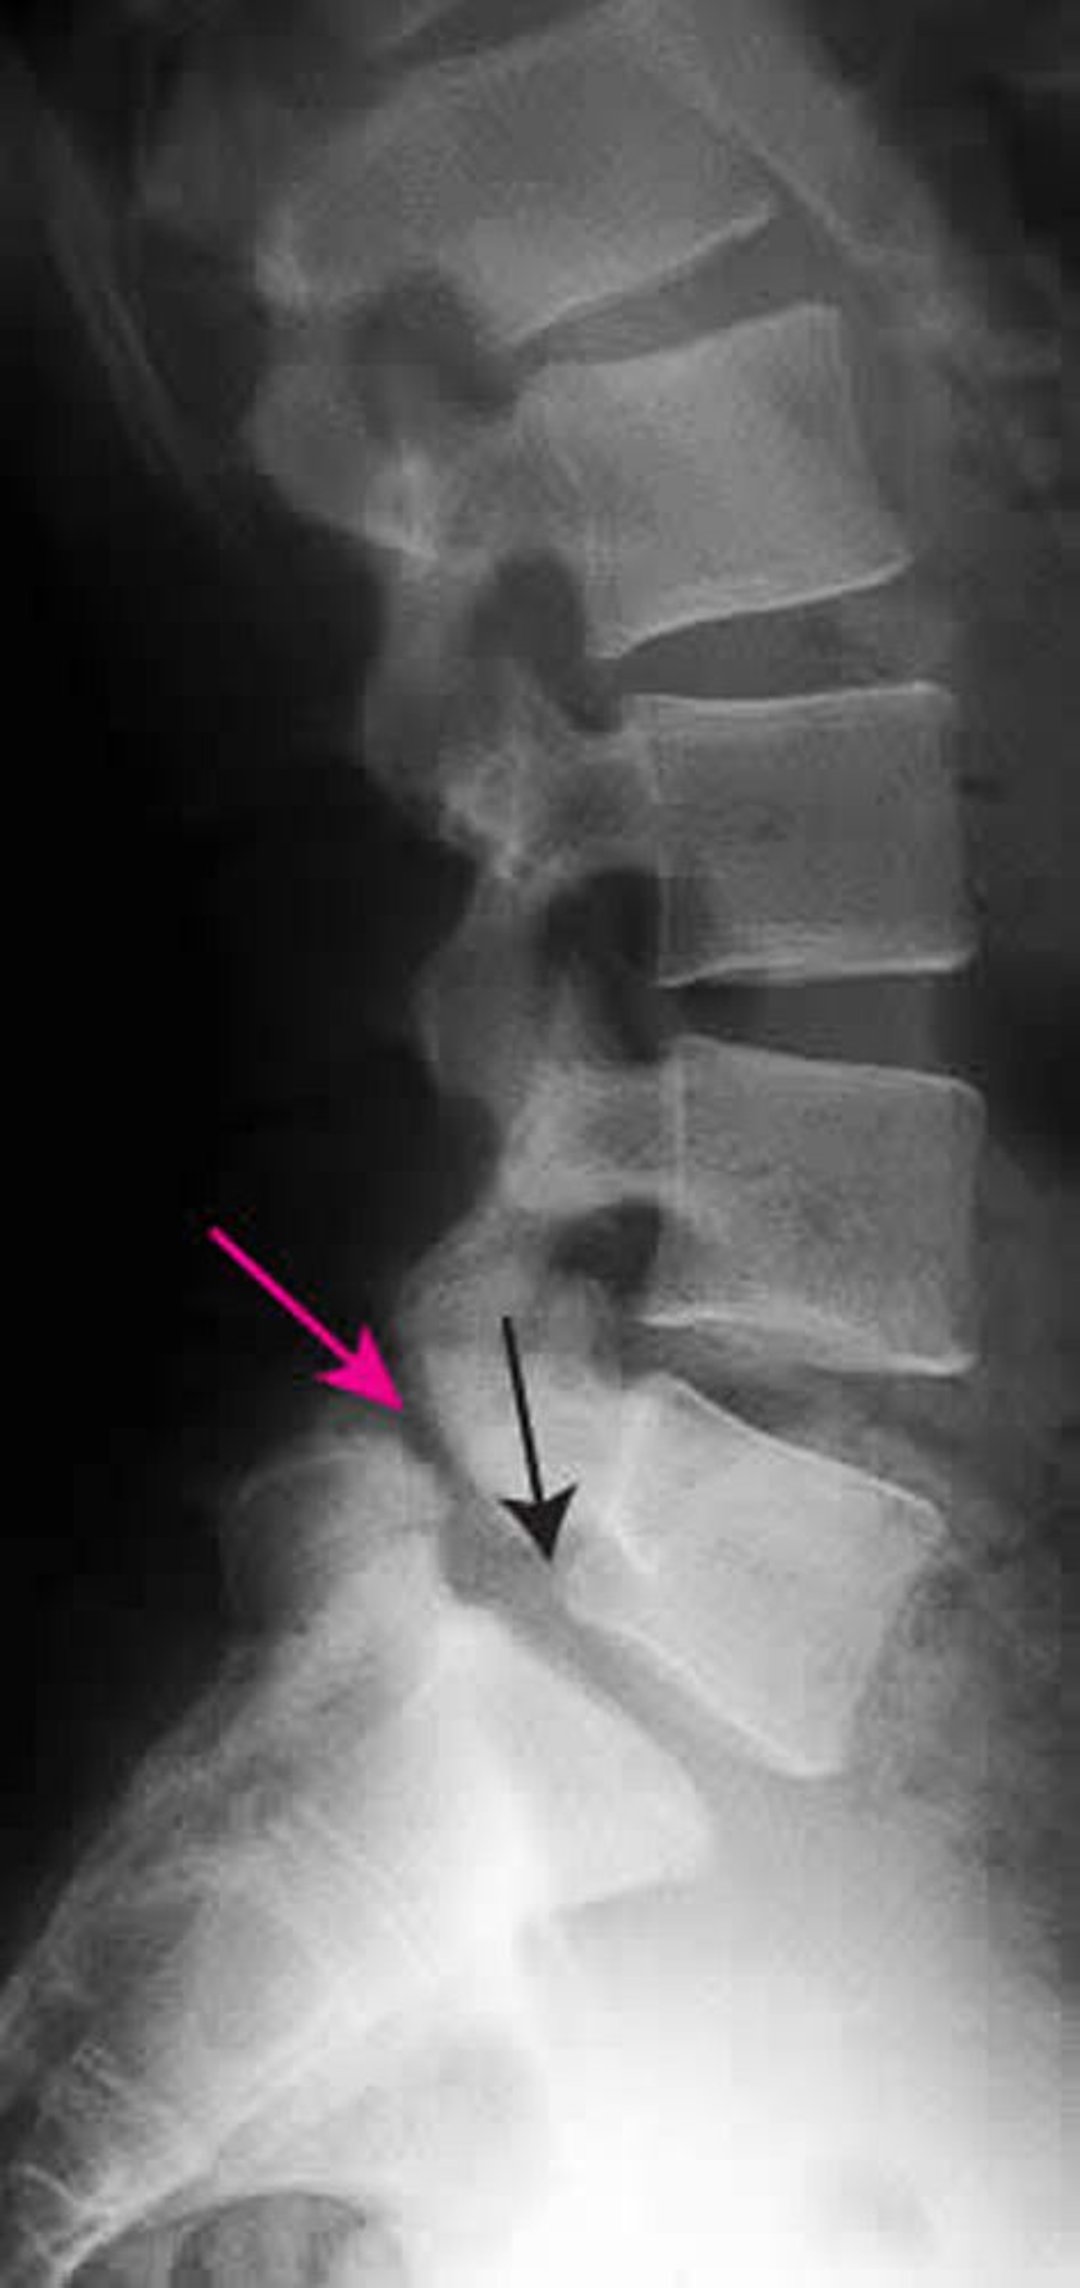

Spondylolisthésis

Cette radiographie montre un spondylolisthésis de grade 1 de L5 sur S1. La flèche noire montre le bord postérieur de L5, qui se subluxe en avant de S1. La flèche rouge pointe un spondylolyse (défaut de la pars interarticularis).

ZEPHYR/SCIENCE PHOTO LIBRARY